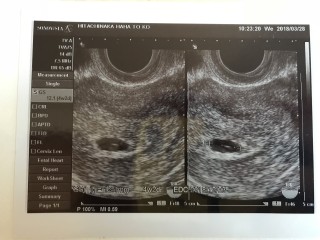

出血や茶おり、ピンクおりが2、3日続いて予約日より早く病院いきました。4w2dでGS6.5ミリ、胎嚢以外は見えなかったけどつわりは毎日あって1人目よりは軽い気がします。

前回は7週で心拍取れず9週で稽留流産だったから今回は無事に育ってほしい!

1人目の時より歳とってる分発育がゆっくりな気がする…